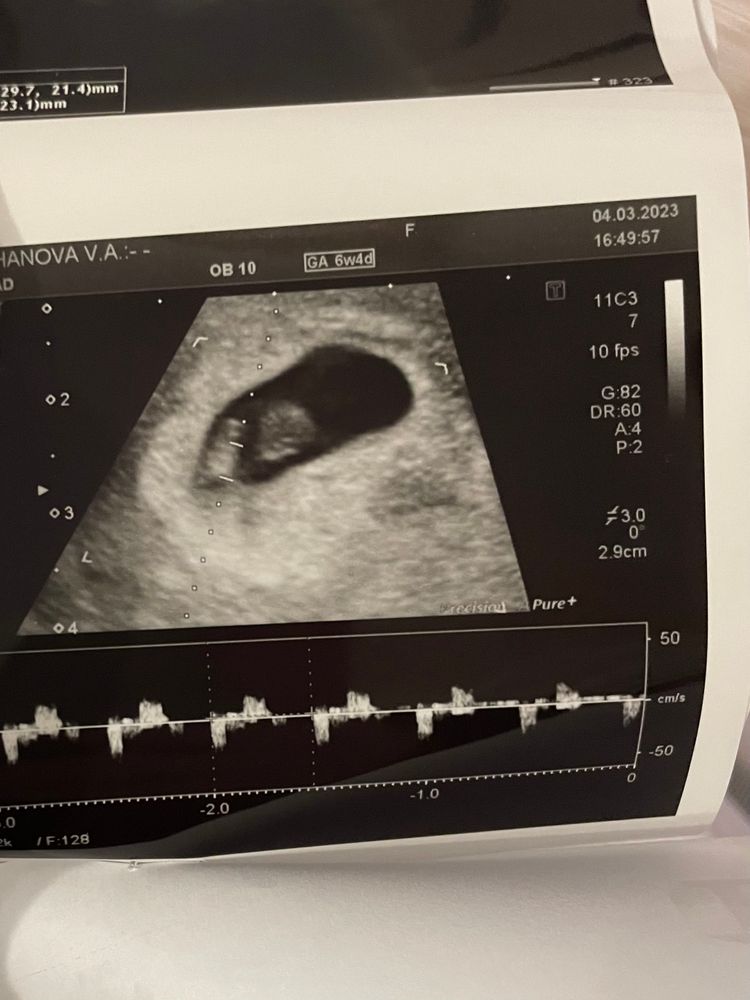

Доброго всем дня! 🌹 в субботу ходила на второе узи) увидели наконец креветку, даже сб наслушали 🤗🤗🤗 на момент узи по месячным срок был 6.5, по узи 6. Сказали, ничего страшного)) я счастлива 🤭🫣 в конце марта пойду на учет вставать 🏃♀️

У меня было так же. На узи в 6+4 ходила, поставили срок 6+1. А к 1 скринингу все день в день было)